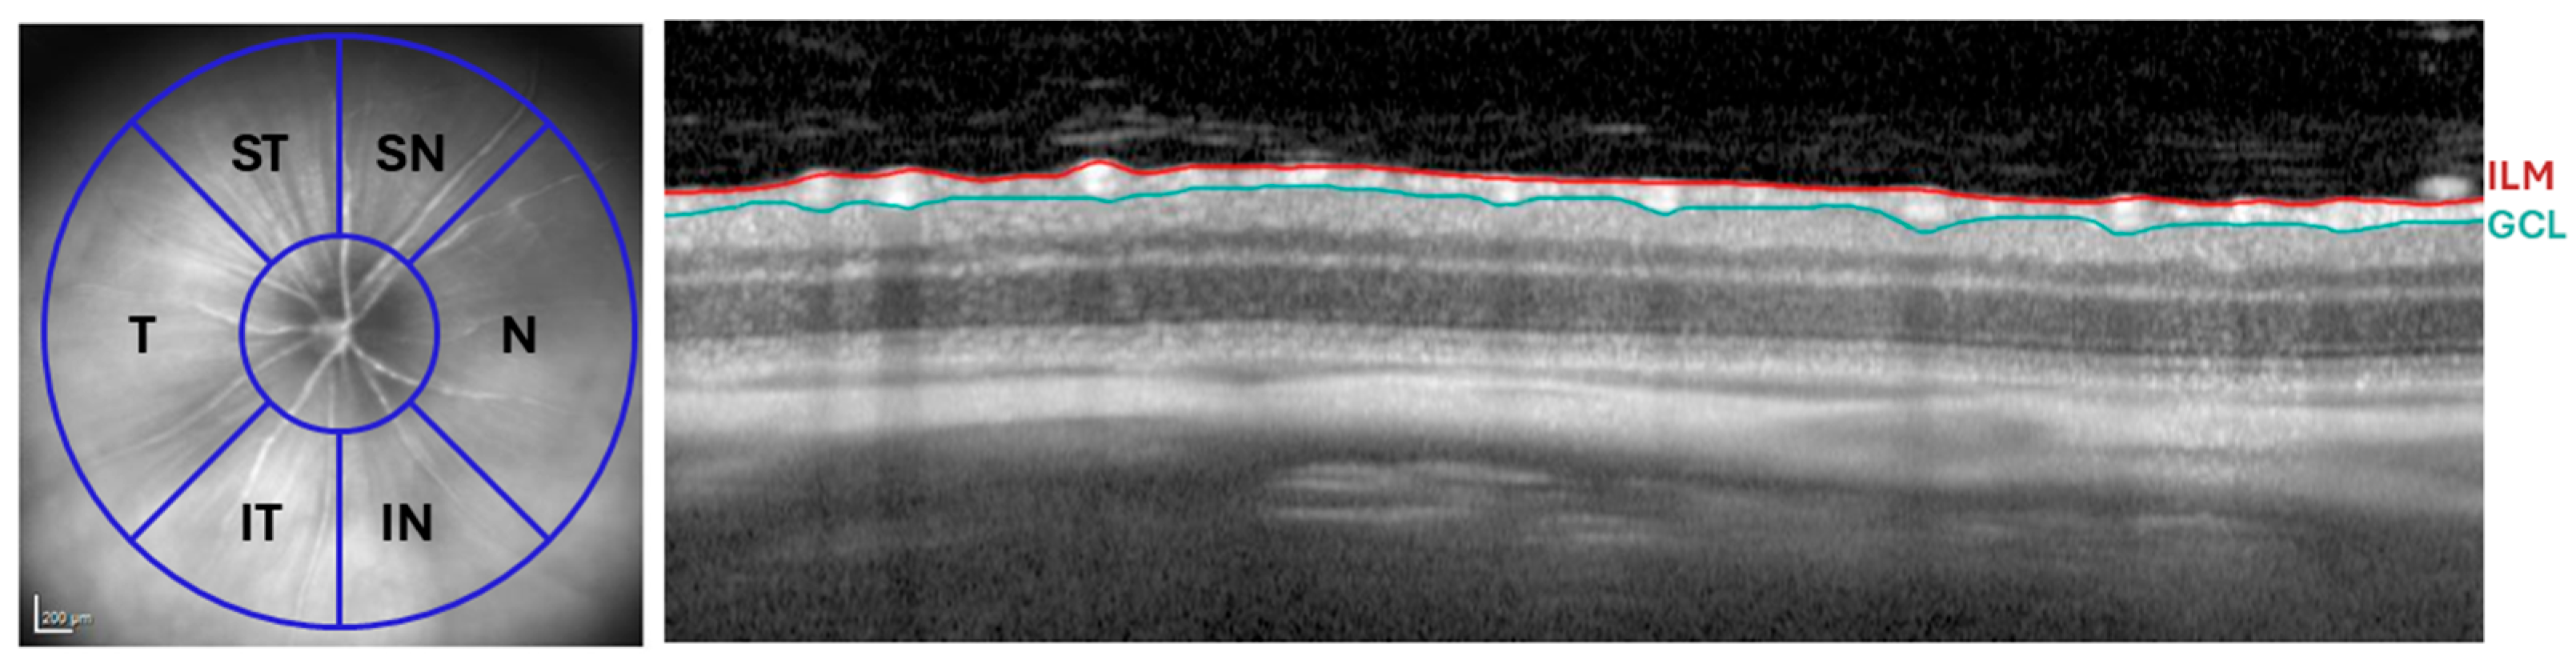

4.7.1. Retinal Thickness Evaluation

4.7.2. Vitreous Particle Quantification